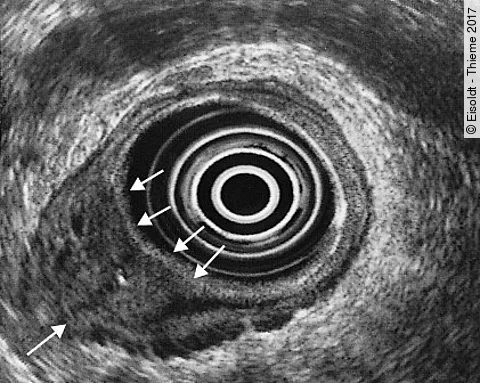

Auflösung Gastro-Quiz

(K)Ein harmoloser Analtumor?

63-jährige Frau mit hellrotem peranalen Blutabgang